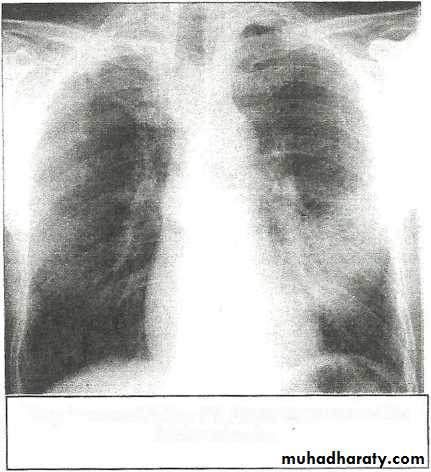

• LOBAR PNEUMONIA

Right lower lobe consolidation - PA. Dense opacification in the right lower zone with effacement of the outline of the right hemidiaphragm.